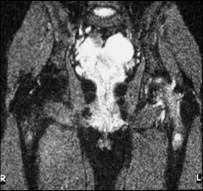

Transient osteoporosis